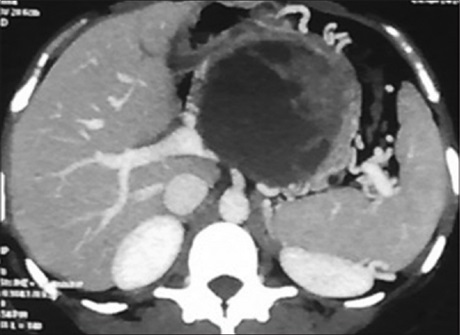

Transarterial Embolization of Nonvariceal Gastrointestinal Bleeding: Our Experience

Dr. Sheo Kumar, Basant Kumar, Archana Gupta, Laxmi Kant Bharti, Anuj Thakral (Author)

56-60